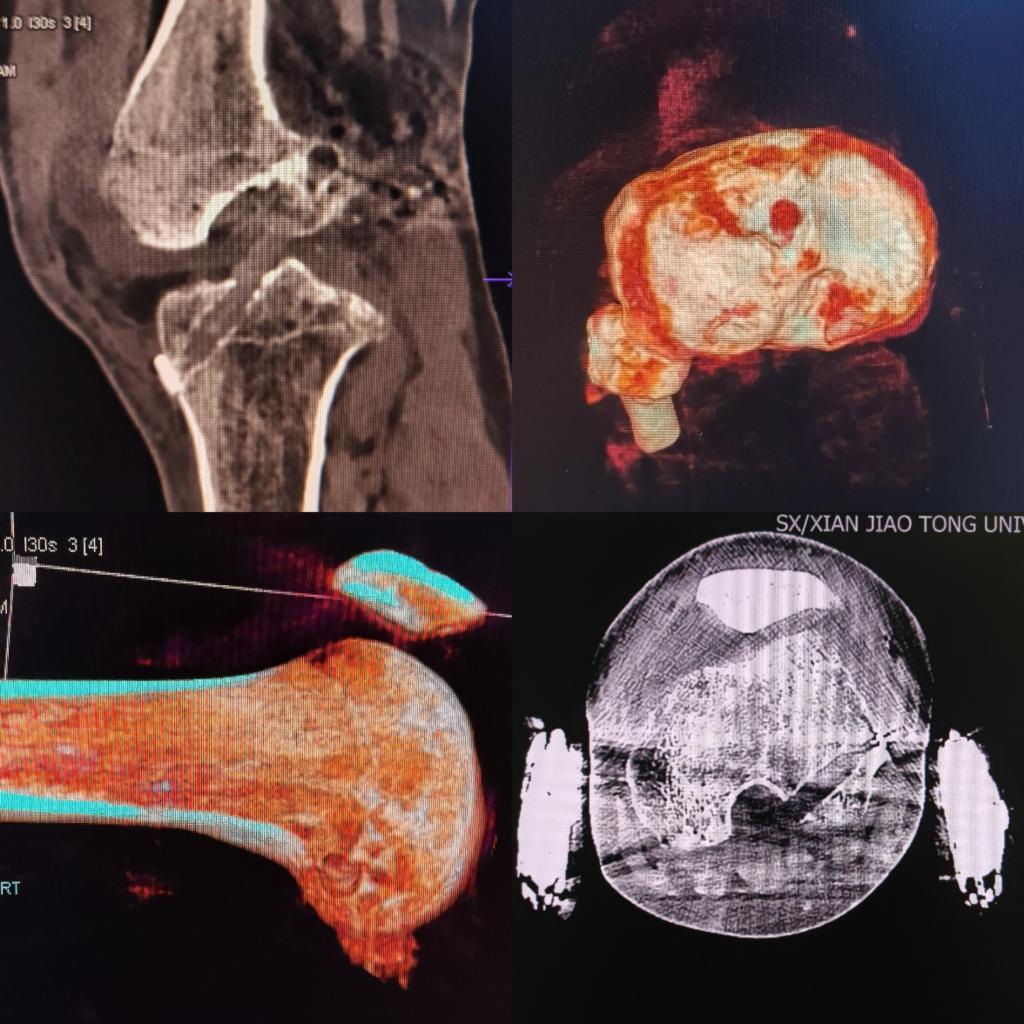

术后复查CT